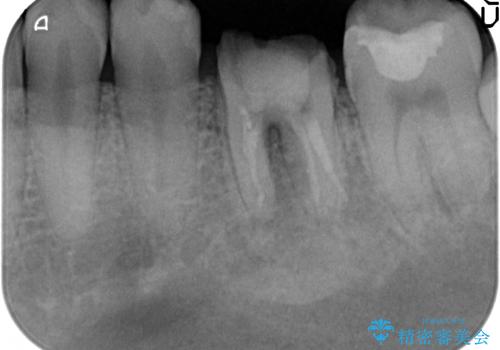

放置してしまった歯 根管治療からの機能回復

- 放置してしまった歯が痛み、いよいよ耐えられなくなり来院されました。

根管治療の途中で放置してしまっていた歯を、最終的に機能回復できるよう治療を行っていきます。

治療途中の歯の放置は、より虫歯を進行させてしまい抜歯に至ってしまうこともあるので注意が必要です。